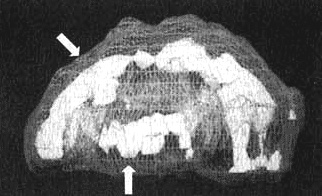

Уилли рассказал мне о двух ДТП и о том, как резко изменился его характер. Я немедленно назначил SPECT. Результаты подтвердили мои опасения. В двух областях обнаружилась повышенная активность — они работали с большой перегрузкой. Одна находилась в левой височной доле, где нарушение функций часто связано с паранойей и насилием. Другая располагалась в верхней средней части фронтальных долей (поясная зона) в той части мозга, которая отвечает за переключение внимания с одного объекта на другой. Когда гиперактивность наблюдается в этой зоне, человек не может переключиться, и мысль его начинает двигаться по спирали. Как только я увидел снимки мозга Уилли, то сразу понял, чем были вызваны все изменения: паранойя, вспыльчивость и негативные мысли о соседе по комнате, от которых он никак не мог отделаться.

Мозг Уилли — травма головы

Трехмерное изображение — активный мозг, вид сбоку. Обратите внимание на выраженное повышение активности в поясной системе и в левой височной доле (см. стрелки).